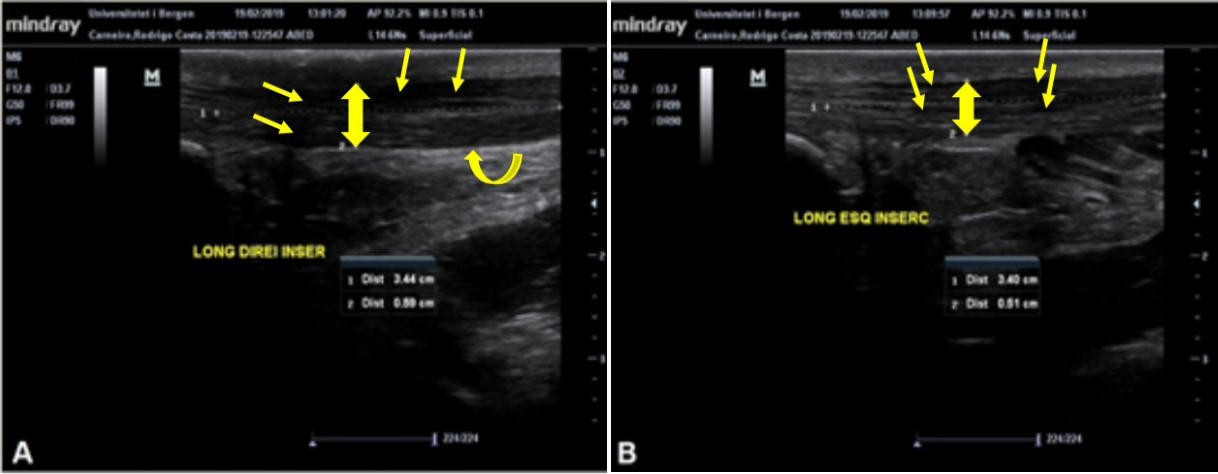

O tendão do calcâneo (TC) é o mais forte tendão do corpo humano, com grande capacidade de suportar carga. O TC é vulnerável a lesões por esforço repetitivo por receber muita carga, responsável por 18% de todas as lesões no esporte. O ultrassom (US) diagnóstico é uma técnica barata, dinâmica e rápida para avaliação de tecidos tendíneos, que pode ser associada a testes clínicos para diagnóstico de tendinopatias. Considerando que a simetria do organismo está relacionada com bom estado geral de saúde, objetivou-se neste trabalho avaliar a morfologia e aspectos clínicos do TC de indivíduos com e sem tendinopatia do TC. Participaram do estudo 28 indivíduos: 15 no grupo controle (GC) e 13 no grupo tendinopatia (GT). Os participantes passaram por avaliações específicas do TC: Exame de US, testes à palpação e clínicos. Os sujeitos do GC apresentam média de 0,407cm e 0,389cm da espessura do TC (TC direito e TC esquerdo), e não foram demonstradas anormalidades que indicassem inflamação nas imagens de US e nos testes clínicos. Nos indivíduos do GT, os valores da espessura do TC foram maiores, atingindo até 0,563cm, além de apresentarem alterações nas imagens de US para inflamação. A diferença da espessura do TC entre membros dos indivíduos do GC foi de 10%, enquanto no GT foi de 22%. Por meio dos resultados, sugere-se que diferenças da espessura do TC superiores a 20% indiquem a presença de tendinopatia, comprovadas pelos achados nas imagens de ultrassom e pelos resultados positivos dos testes à palpação e clínicos.Downloads